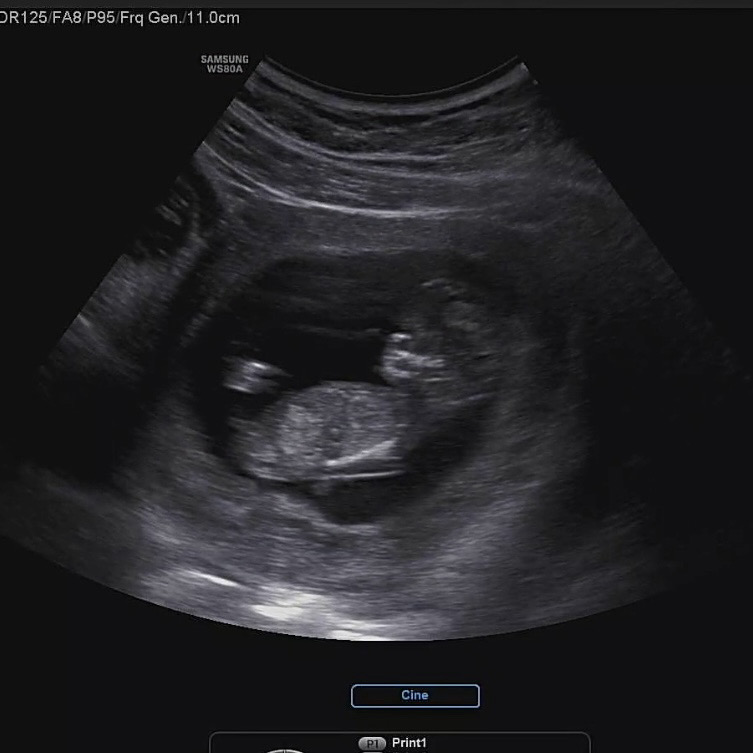

12주 3일 각도법 봐주세요🫶🏼

아들일까요..?